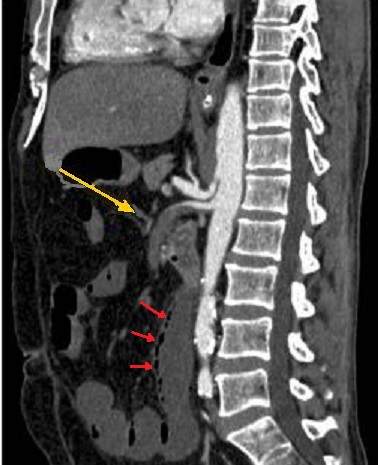

Image d'une thombus de artere

mesenterique superieure ( ischemie meresenterique

arterielle aigue ) en TDM phase arterielle ,coupe

sagitale . Sur cette coupe on peut

voyait ảrtere du tronc coeliaque en net et complete

, artere mesenterique superieure est en se voyait

encore d'une partie seul a hyper-dense . Image du

thrombus est iso-dense ( fleche jaune ) . Aspect de

pneumomatose de la paroi de l'intestin est encore se

voyait sur une portion verticale de l'intestin (

fleche rouge ) . Ischemie mesenterique arterielle

aigue en coupe TDM sagitale . |